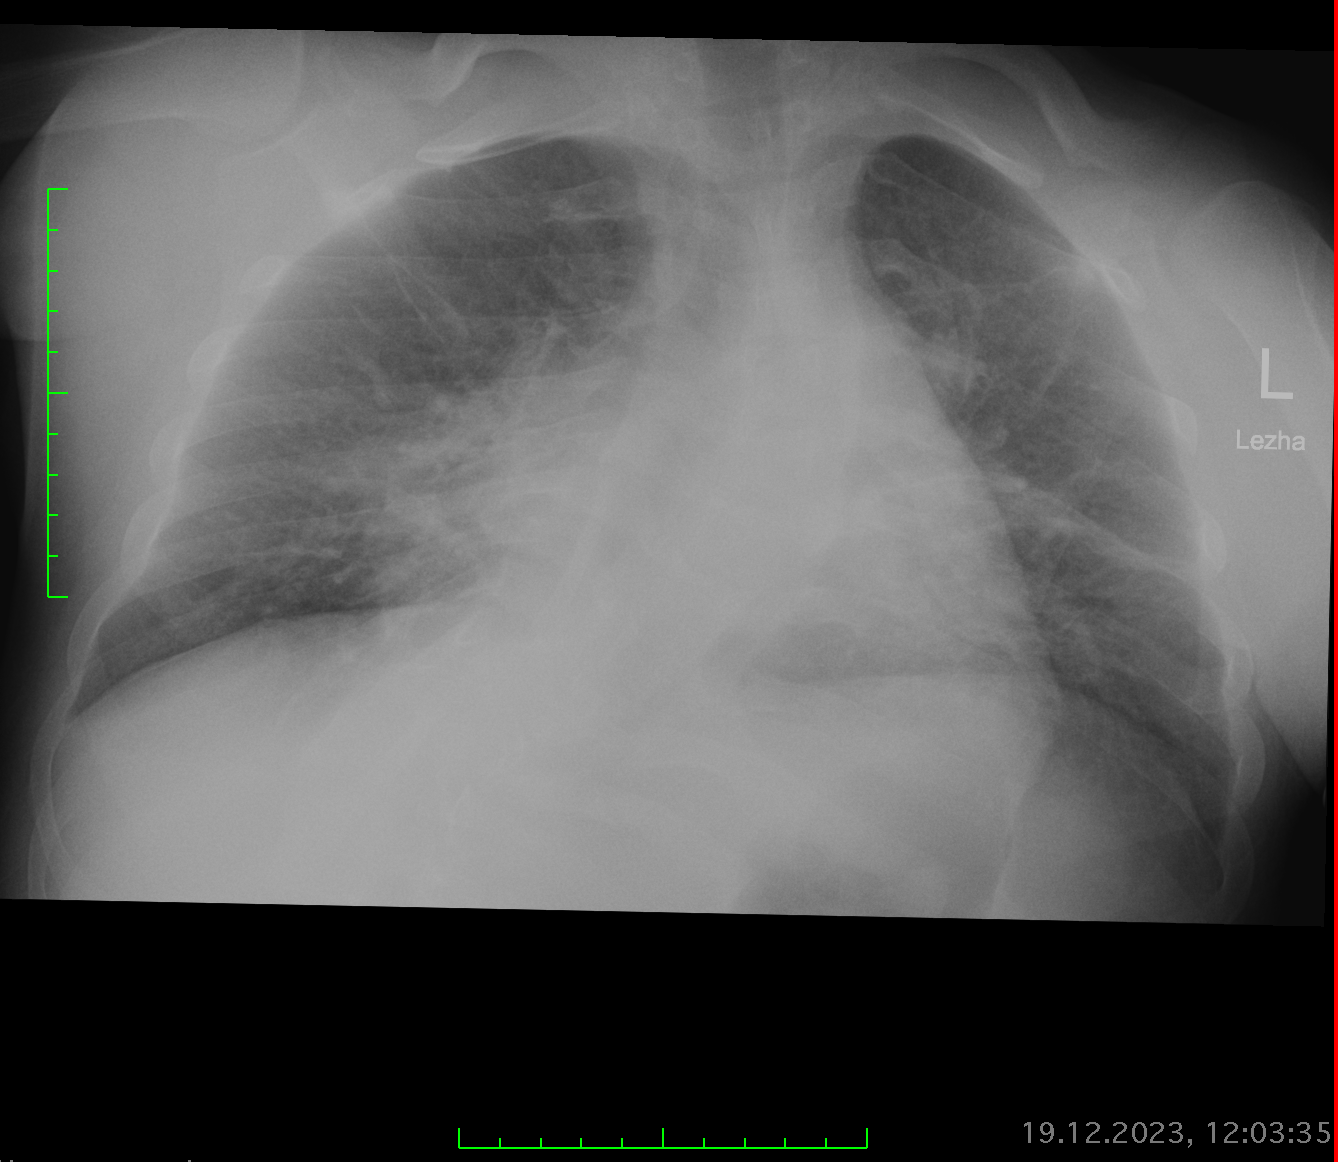

Женщина 1956 года. Направлена для исключения пневмонии. Это гидроторакс или ателектаз? Средостения смещено вправо или это за счёт разворота?

77. Пневмония?

Добрый день! Бокового к сожалению нет. Как на ваш взгляд, справа больше на пневмонию похоже? Либо обструктивный ателектаз?

Добрый день. Подскажите пожалуйста, в верхних отделах правого легкого линейная тень. что это может быть : фиброзные изменения или дисковидный ателектаз. ? Спасибо